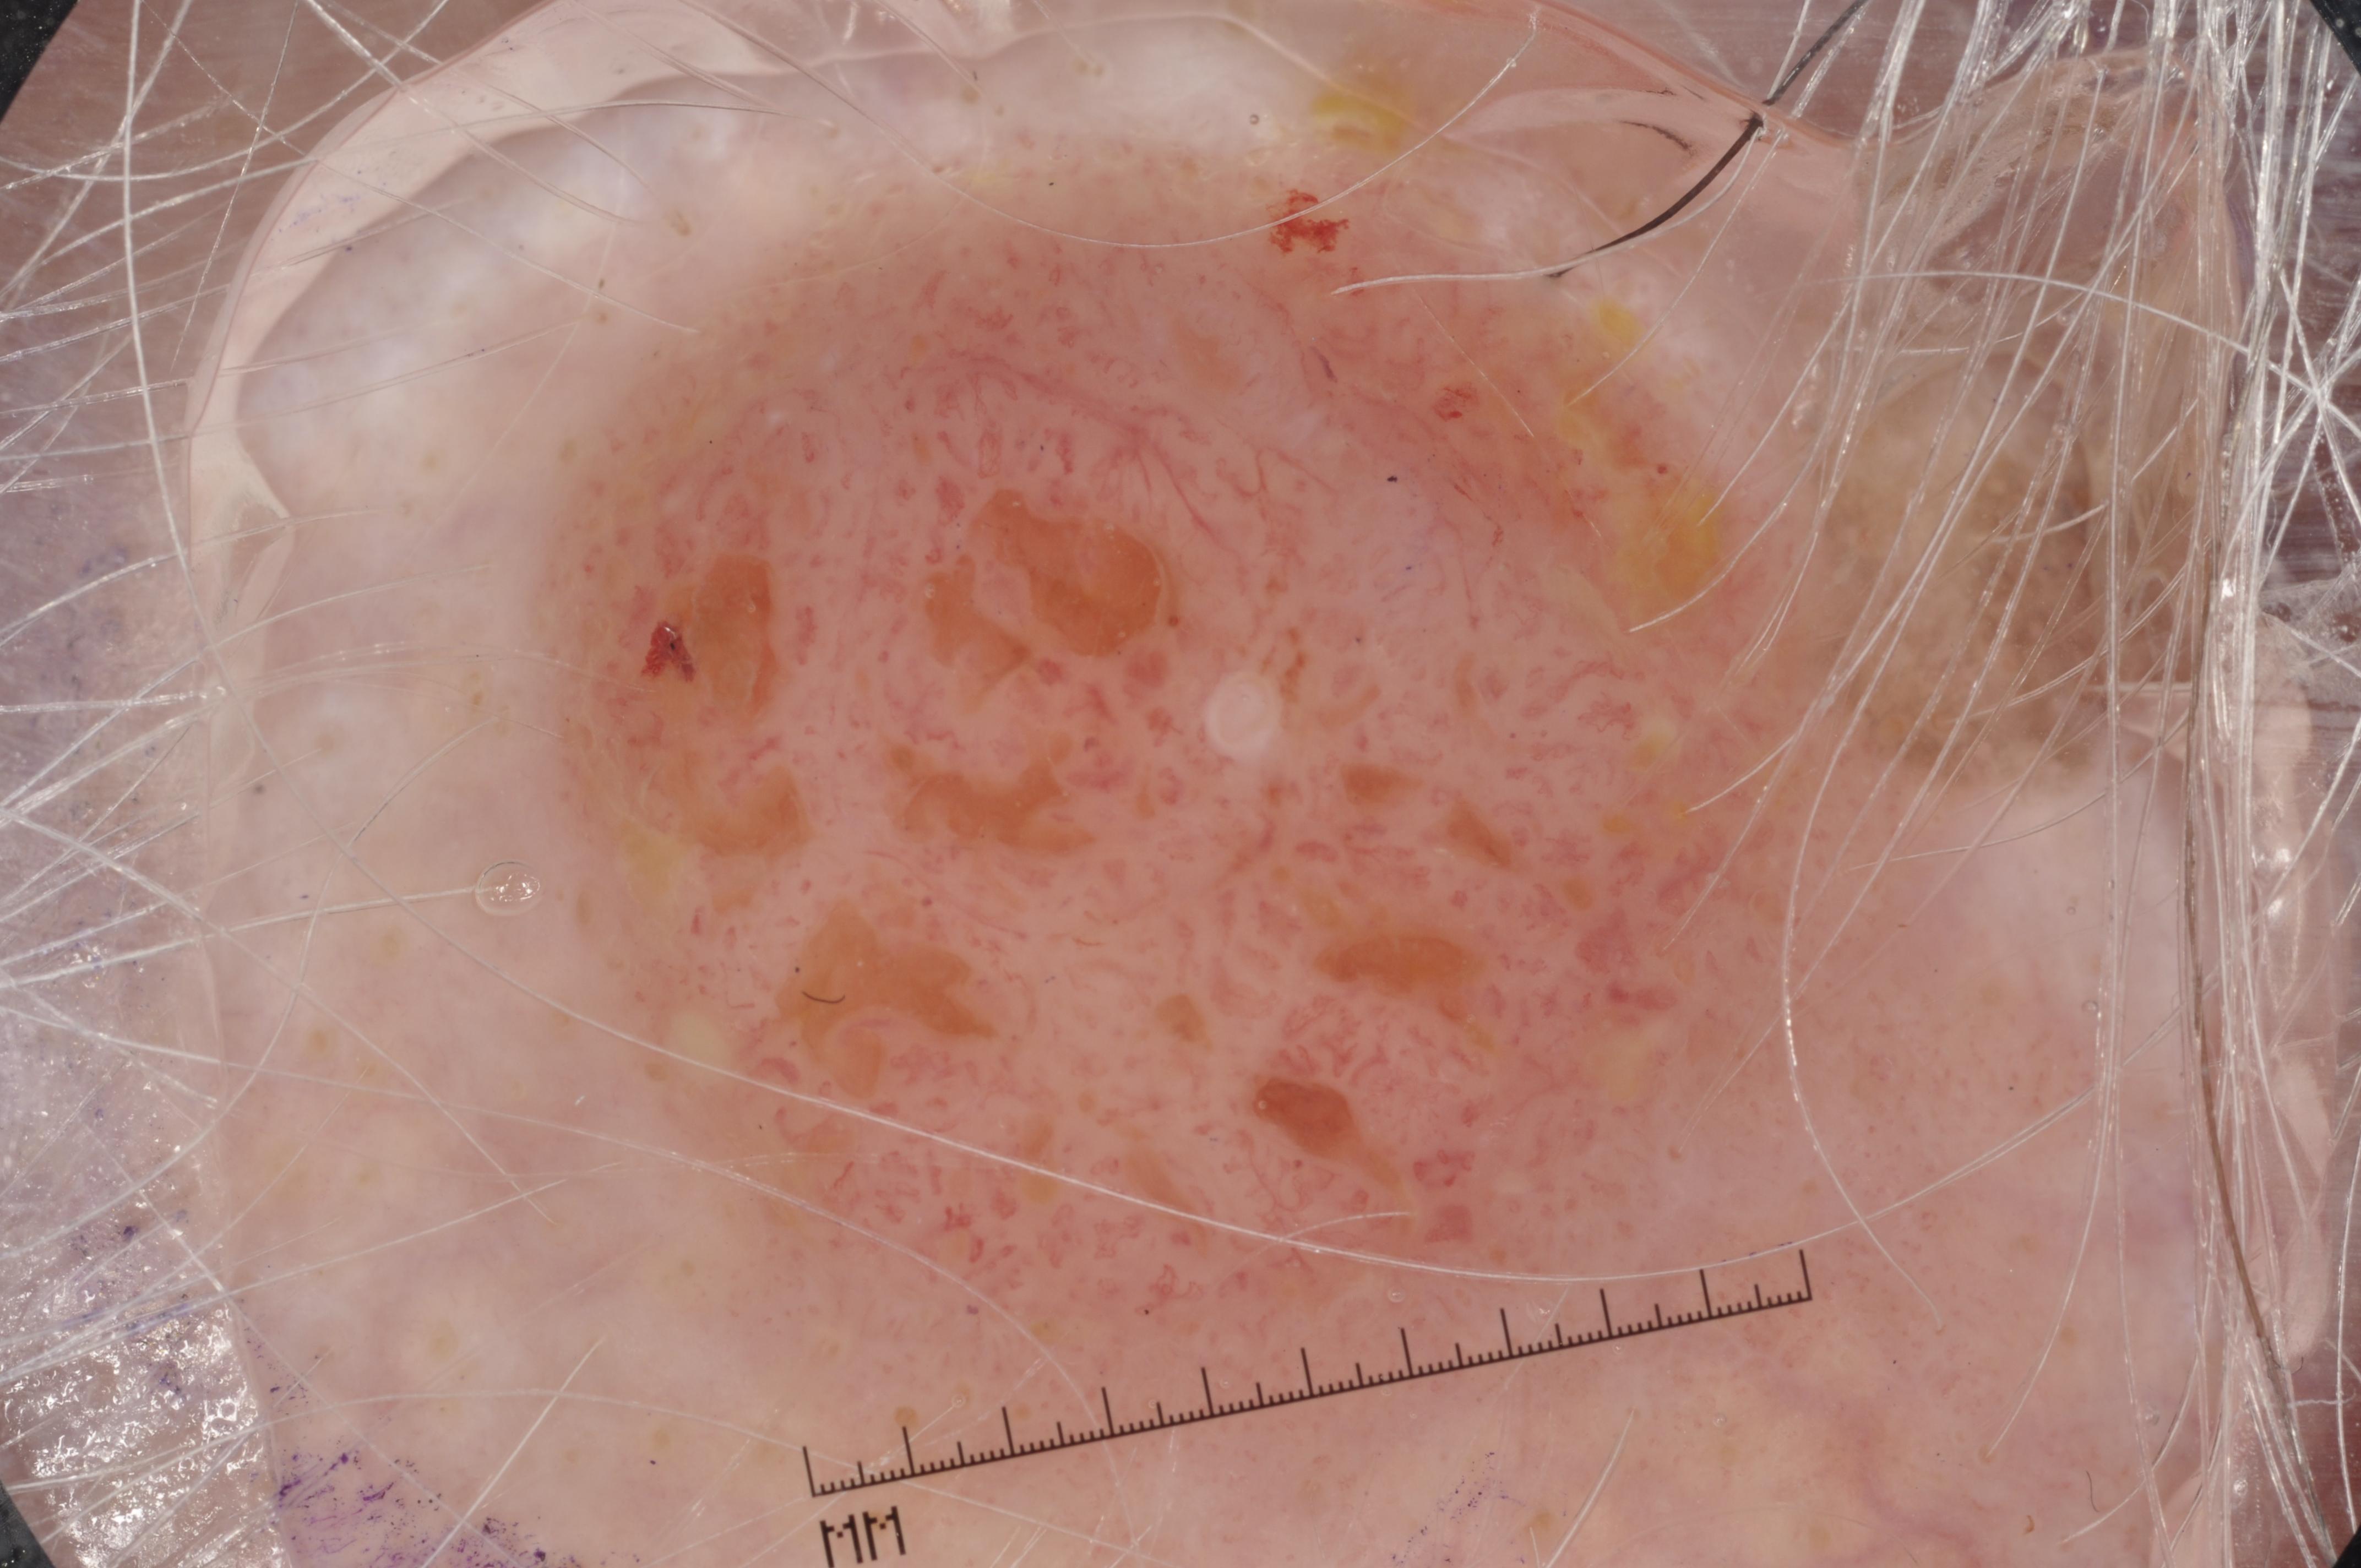

{

"age_approx": 85,

"anatom_site_general": "lower extremity",

"concomitant_biopsy": true,

"dermoscopic_type": "contact non-polarized",

"diagnosis_1": "Malignant",

"diagnosis_2": "Malignant epidermal proliferations",

"diagnosis_3": "Squamous cell carcinoma, NOS",

"diagnosis_confirm_type": "histopathology",

"image_type": "dermoscopic",

"lesion_id": "IL_0375857",

"melanocytic": false,

"sex": "male"

}